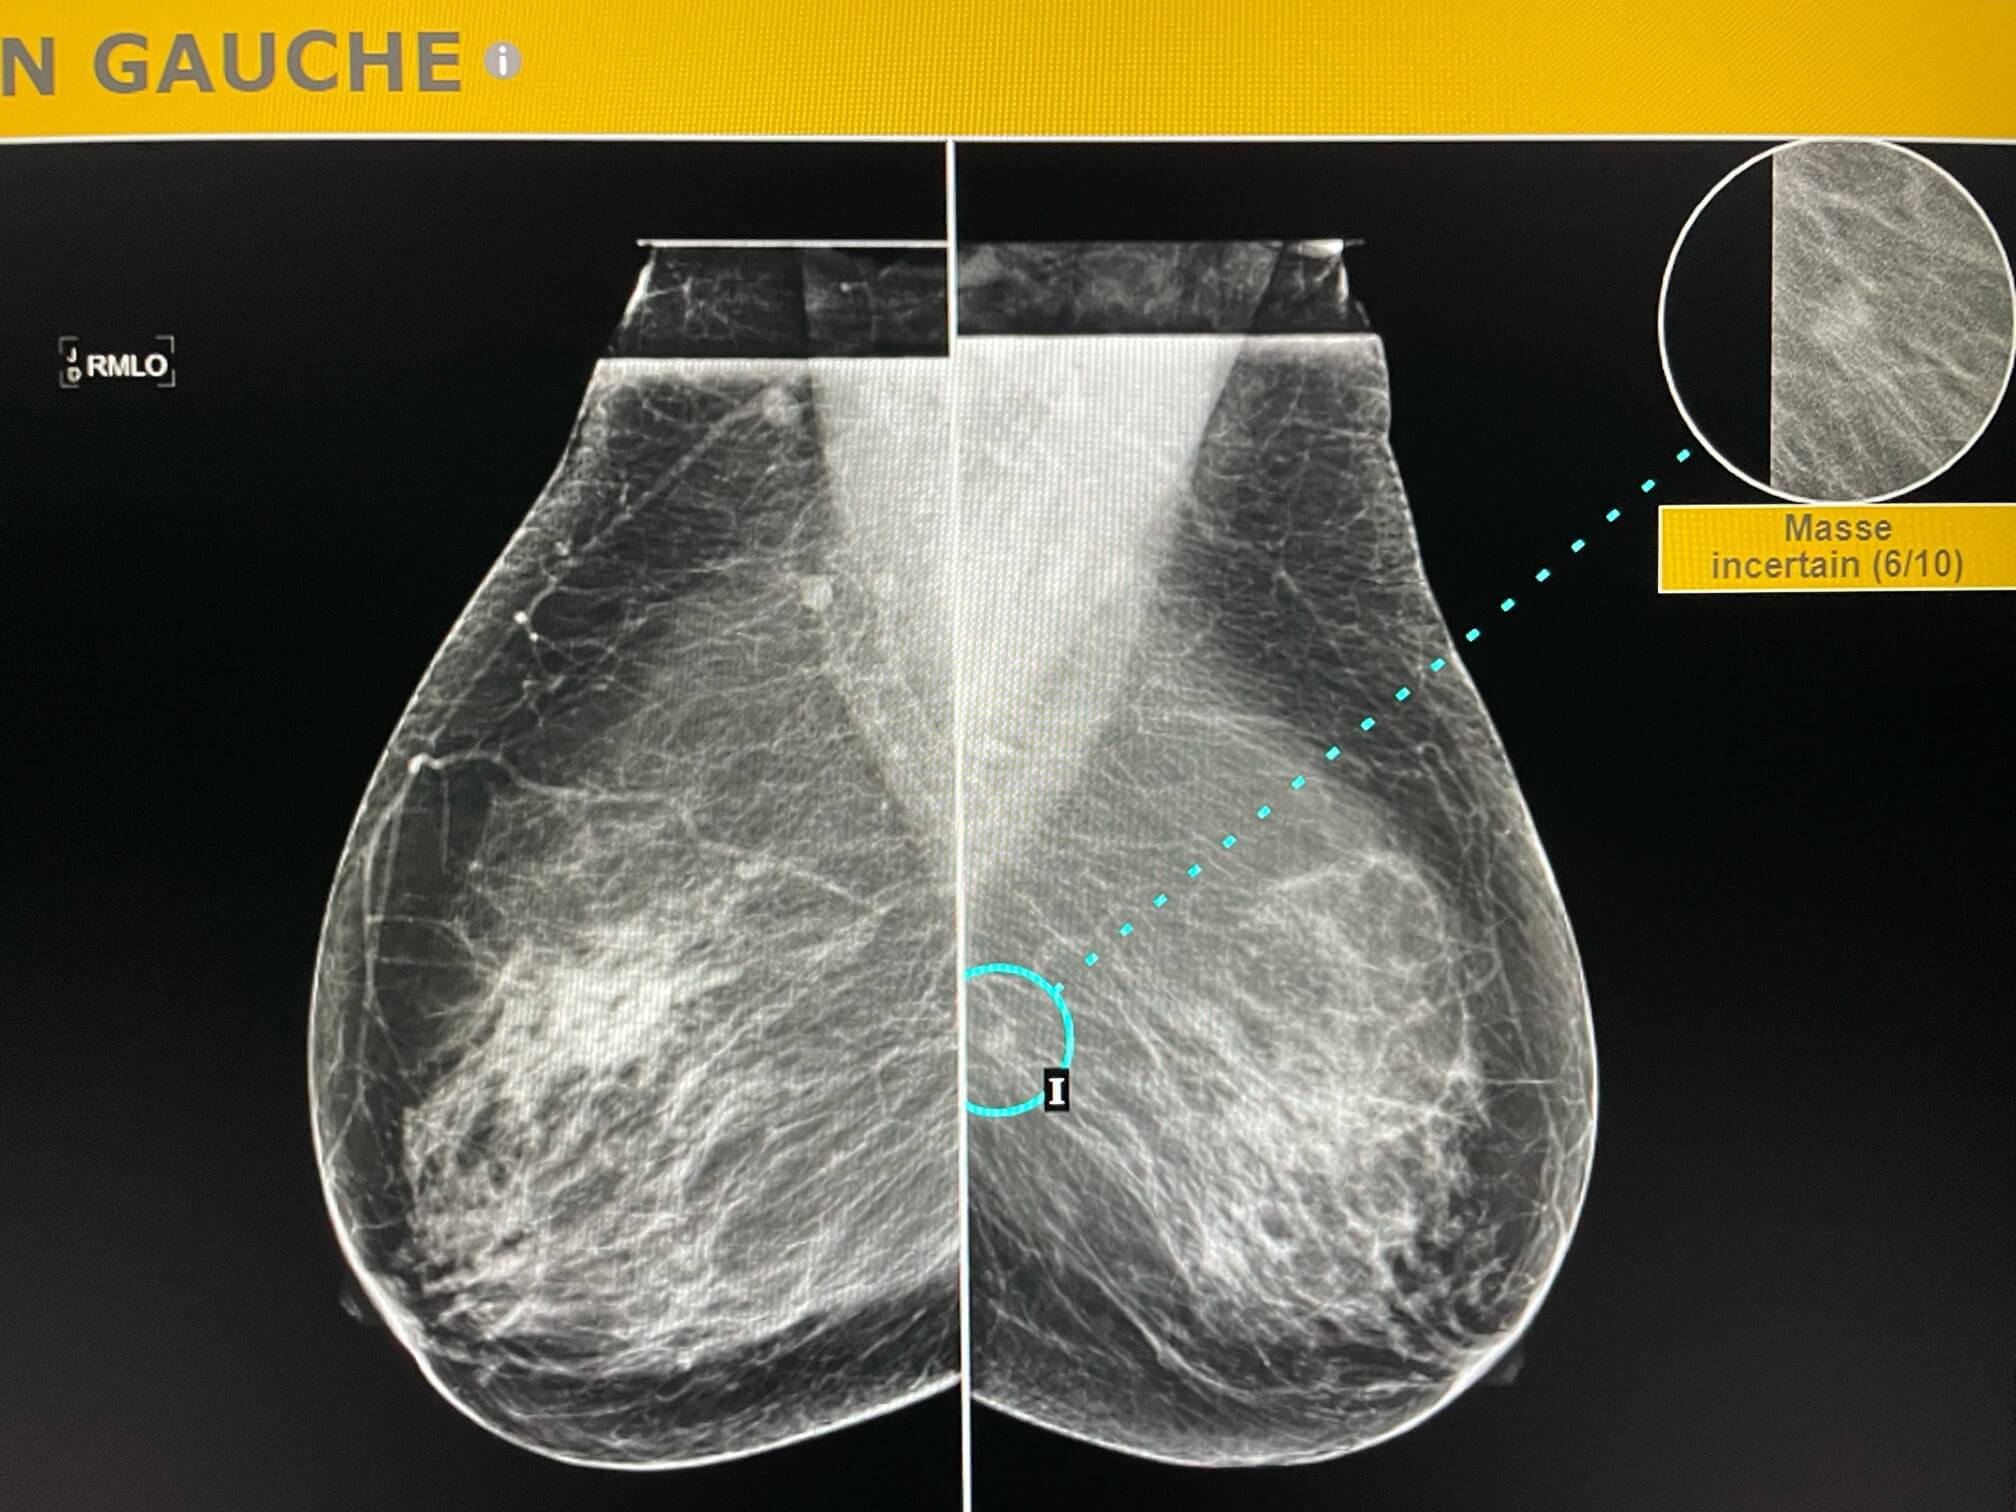

Mammoscreen pointe un surcroît de densité supéro interne du sein gauche.